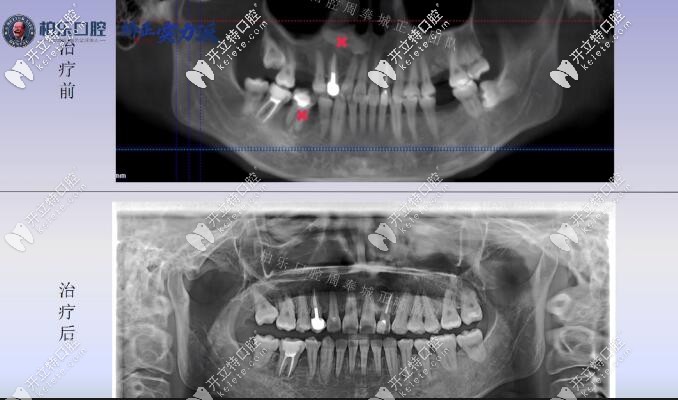

看看南寧柏樂(lè)口腔醫(yī)院缺失3顆大牙的牙齒矯正案例是個(gè)什么情況:

癥狀:上牙左右各缺失了一顆大磨牙,下牙左側(cè)缺失一顆大牙;并且從X線片看,上頜唇側(cè)的前牙位置上有一顆多生牙是需要拔除的,還有一顆阻生智齒。顧客也沒(méi)想到自己30歲了還能長(zhǎng)智齒。

看看整個(gè)案例矯正前后的X線片對(duì)比,竟然連智齒也扶正了。

紅叉的地方就是多生牙的位置和沒(méi)有保留價(jià)值的大牙。

從矯正x線片對(duì)比基本可以看出來(lái)其實(shí)難度較大的是智齒豎直,現(xiàn)在治療已經(jīng)結(jié)束,從智齒的位置可以看出來(lái):基本已經(jīng)扶正是可以使用的功能牙。